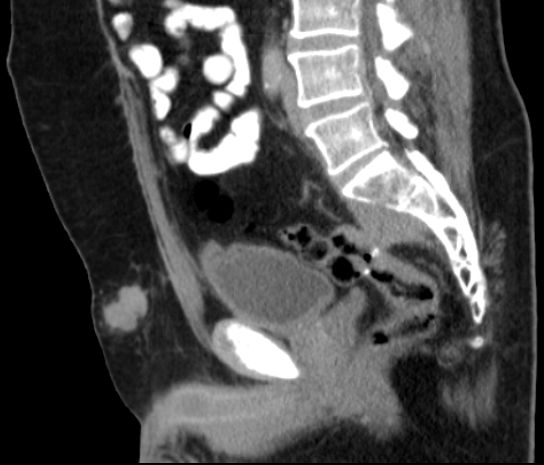

| Bauchdecken - Metastase | 59-jähriger Mann, bei dem vor 3 Jahren ein Sigmakarzinom Z3d No Mo operiert wurde.

Post OP 6x FOLFOX 4. Jetzt Bauchdeckenmetastase, Lungenmetastasen, Arrosion der LWS.![]() |

![]() | |